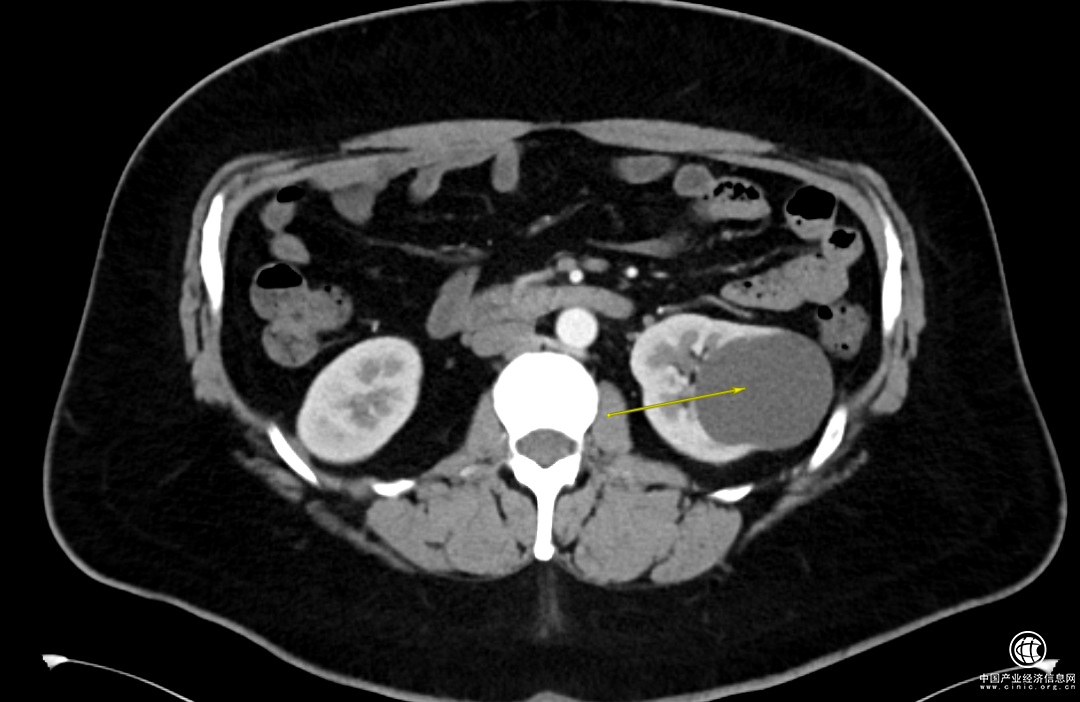

1个月前,Adam感觉到左侧腰背部偶尔会有阵发性胀痛不适的情况,于是做了泌尿系彩超,发现左肾的囊肿已经超过6cm了。

经过一系列的检查,詹绍洋主任诊断Adam是单纯性肾囊肿,安排住院。

詹绍洋主任决定在全麻下行腹腔镜下左肾囊肿去顶术,将肾囊肿囊壁进行切除,切除这部分囊壁后原先肾囊肿的完整性就被破坏,它的张力也就随之消失,切除囊壁的肾脏部位就基本不会再次积聚囊液产生压力从而再次形成囊肿。